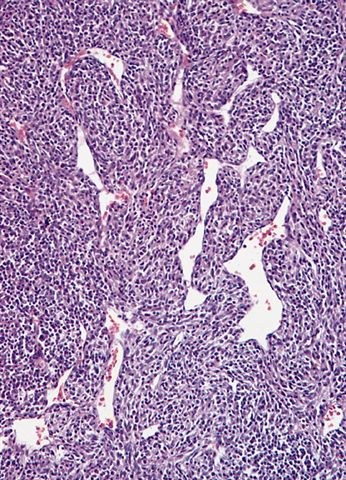

Microscopic (histologic) description

- High grade dedifferentiated liposarcoma

- Dedifferentiated component is a cellular and typically a nonlipogenic sarcoma with significant pleomorphism

- Heterologous elements in 5 - 10% of cases

- Heterologous elements can easily mislead pathologists in poorly sampled cases, especially in metastatic sites

- Can manifest as neural differentiation, leiomyosarcoma, osteosarcoma / chondrosarcoma, rhabdomyosarcoma or pleomorphic liposarcoma (homologous lipoblastic dedifferentiation)

Microscopic (histologic) images

Contributed by Michael R. Clay, M.D. and AFIP